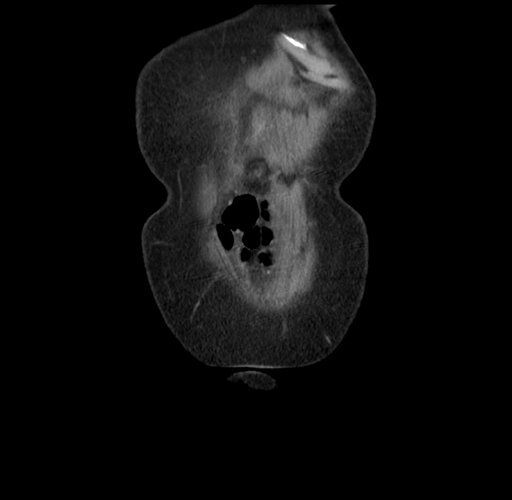

Pre-Chemo: Axial Venous

Axial Venous